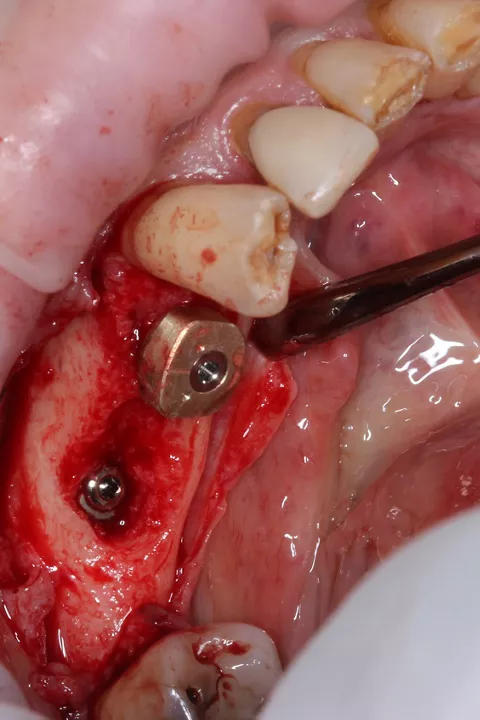

5a. 5b. Digitally guided osteotomy and implant placement on LL4 (Lower LEFT 4) and LL5 (Lower LEFT 5) 0.5mm sub-crestal performed using the Integral Kit, following the manufacturer’s drilling sequence and implant placement protocol after flap elevation.

In the posterior left mandible, bone conditions varied across sites and dictated different healing protocols. At LL5, the initial panoramic radiograph showed evidence of a previous extensive infection, resulting in compromised bone quality. Despite under‑preparing the osteotomy to improve implant engagement, adequate primary stability could not be achieved; therefore, the implant was placed subcrestally and covered to allow undisturbed osseointegration under a submerged healing protocol.

In contrast, the adjacent LL4 site presented more favorable bone conditions and achieved high primary stability at placement, enabling immediate placement of a HealFit® anatomical healing abutment to establish transmucosal shaping from surgery. After 3 months, osseointegration was satisfactory at both sites, though soft‑tissue maturation was notably superior at LL4, consistent with early guided soft‑tissue contouring.

Similarly, at LL6 the implant exhibited insufficient primary stability (< 20 N·cm) and was placed subcrestally with a cover screw for submerged healing, while the mesial implant at LL5 (when stability was adequate > 45 N·cm) received a HealFit® abutment to support soft‑tissue maturation during healing (7.).